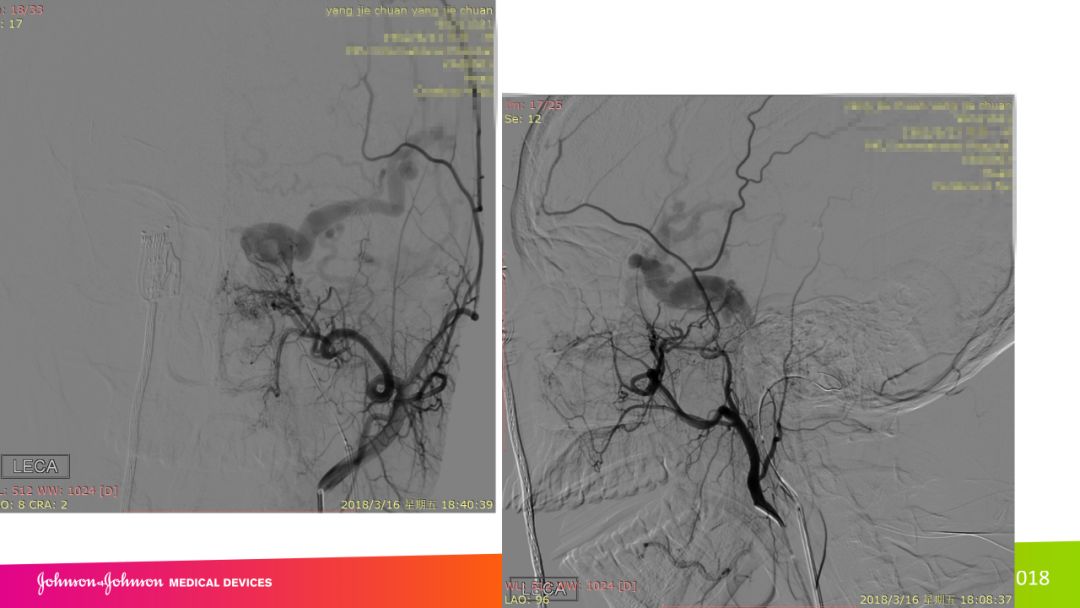

复合手术治疗海绵窦区硬脑膜动静脉瘘一例